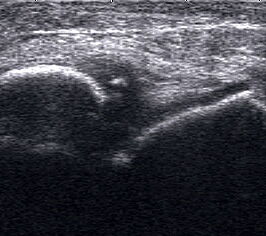

Echogene Verdickung im Subkutangewebe bei Lymphödem

Abbildung 8

Lagerung: Rückenlage.

Schnittebene: Ventraler LS über dem OSG.

Referenzstrukturen: Distale Tibia und Talusrolle, darüber Gelenkkapsel. Befunde: Echogene Verdickung subkutan (Abb. 8), hier peronäal oberhalb des OSG. Bei Varicosis sind in der Subkutis erweiterte Venenkomplexe mit echoarmem Lumen und positivem Doppler-Signal zu sehen.